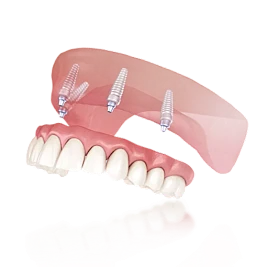

Установили 4 импланта сверху и 4 импланта снизу

- Имплантация, установка временного протеза

- Проверка стабильности установки имплантов

- Установка постоянного протеза